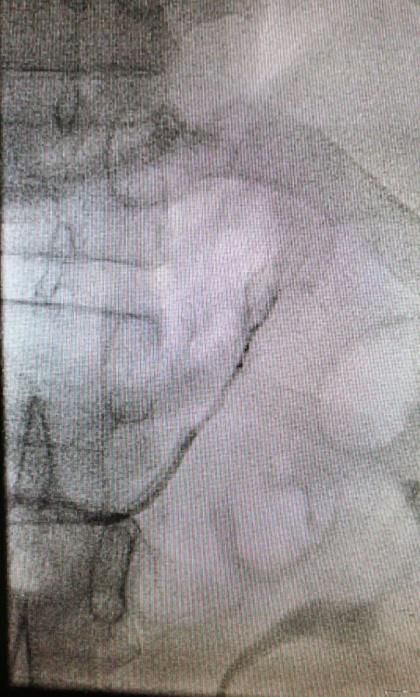

右側腎上腺靜脈插管